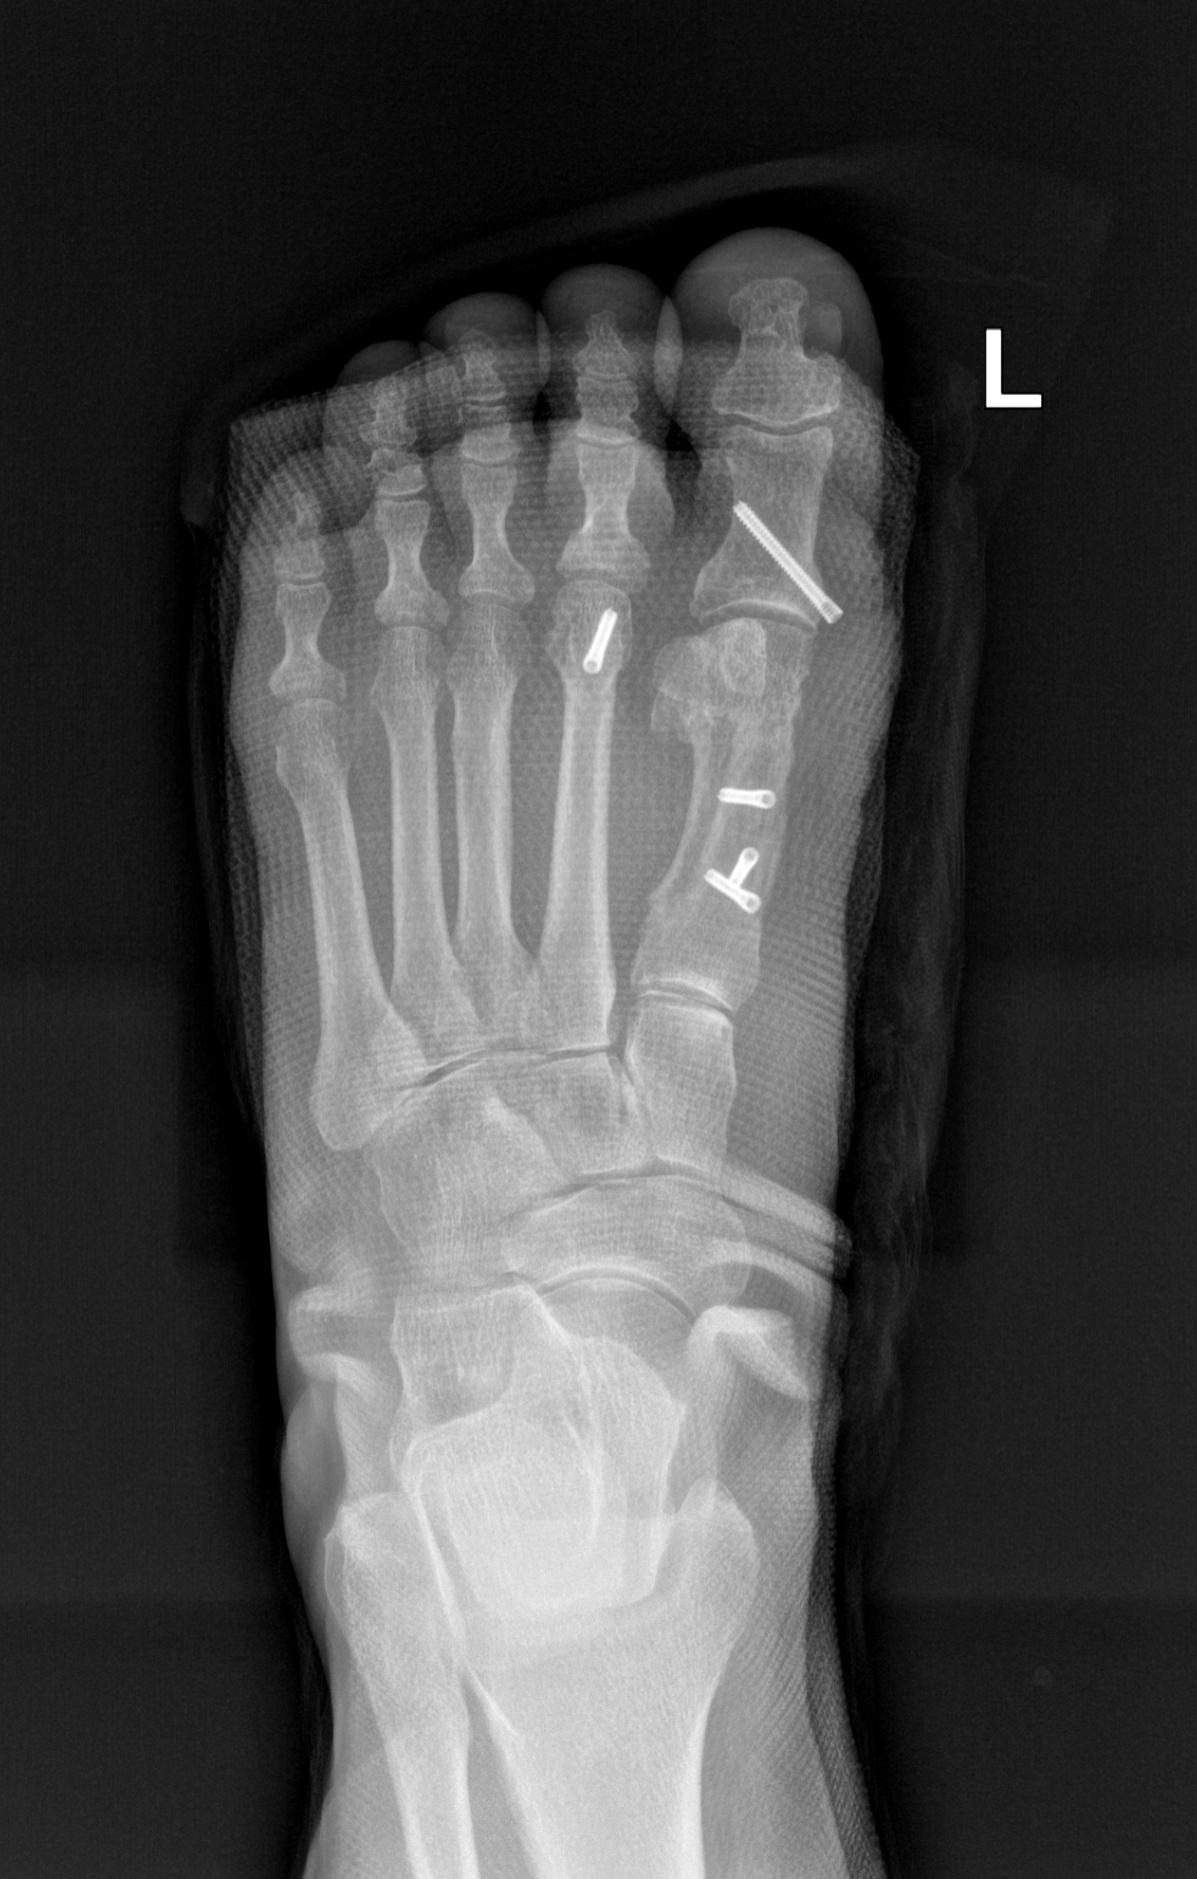

术后影像

术后